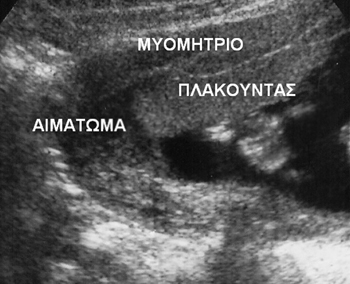

Η πρόωρη αποκόλληση του πλακούντα επιπλέκει περίπου το 1% των κυήσεων. Μπορεί

να συνοδεύεται από κλινική συμπτωματολογία όπως κοιλιακό άλγος, κολπική αιμόρροια

και ευαισθησία της μήτρας (εικόνα 4). Παράγοντες κινδύνου είναι η υπέρταση,

το κάπνισμα, η χρήση κοκαΐνης, ο τραυματισμός, η πρόωρη ρήξη υμένων και οι ανωμαλίες

της μήτρας.(3) Η δυσμενής πρόγνωση οφείλεται σε αιμορραγία που περιλαμβάνει

το 30-40% του πλακούντα και μπορεί να οδηγήσει σε ενδομήτρια υπολειπόμενη ανάπτυξη

του εμβρύου, ολιγάμνιο και πρόωρο τοκετό.(7) Η ευαισθησία των υπερήχων στην

απεικόνιση του οπισθοπλακουντιακού αιματώματος είναι μόνο 50%, επειδή παρουσιάζει

ποικίλη μορφολογία ανάλογα με το σημείο, την έκταση και το χρόνο που έχει περάσει

από το επεισόδιο. Τα υπερηχογραφικά χαρακτηριστικά της πρόωρης αποκόλλησης του

πλακούντα αναφέρονται στον πίνακα 3.(8)

Εικόνα 4. Αιμάτωμα πλακούντα.